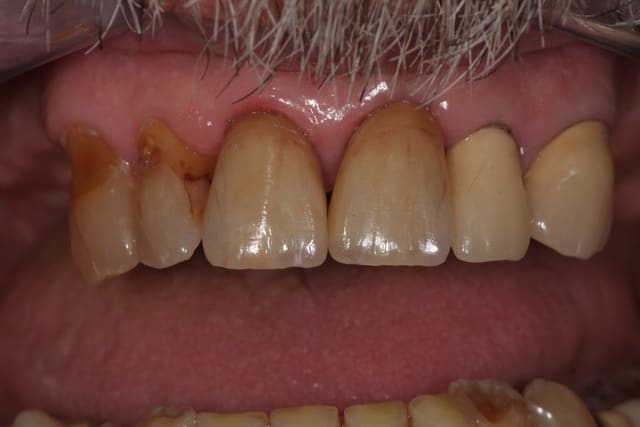

J'ai posé un autre cas d'Emax avant hier pas trop mal, patient content.

Sur 21 très large sur laquelle j'ai fait apexification au MTA.

(Sur la photo, ce n'est pas un herpes, mais une chute en luge au ski...)

Variolink II teinte A3